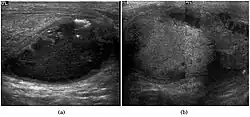

Fig. 5. Teratoma. A plaque-like calcification with acoustic shadow is seen in the testis. -

Fig. 6. Mature cystic teratoma. (a) Composite Image. Mature cystic teratoma in a 29-year-old man. Longitudinal sonography image of the right testis shows a multilocular cystic mass. (b) Mature cystic teratoma in a 6-year-old boy. Longitudinal sonography of the right testis shows a cystic mass containing calcification with no obvious acoustic shadow.